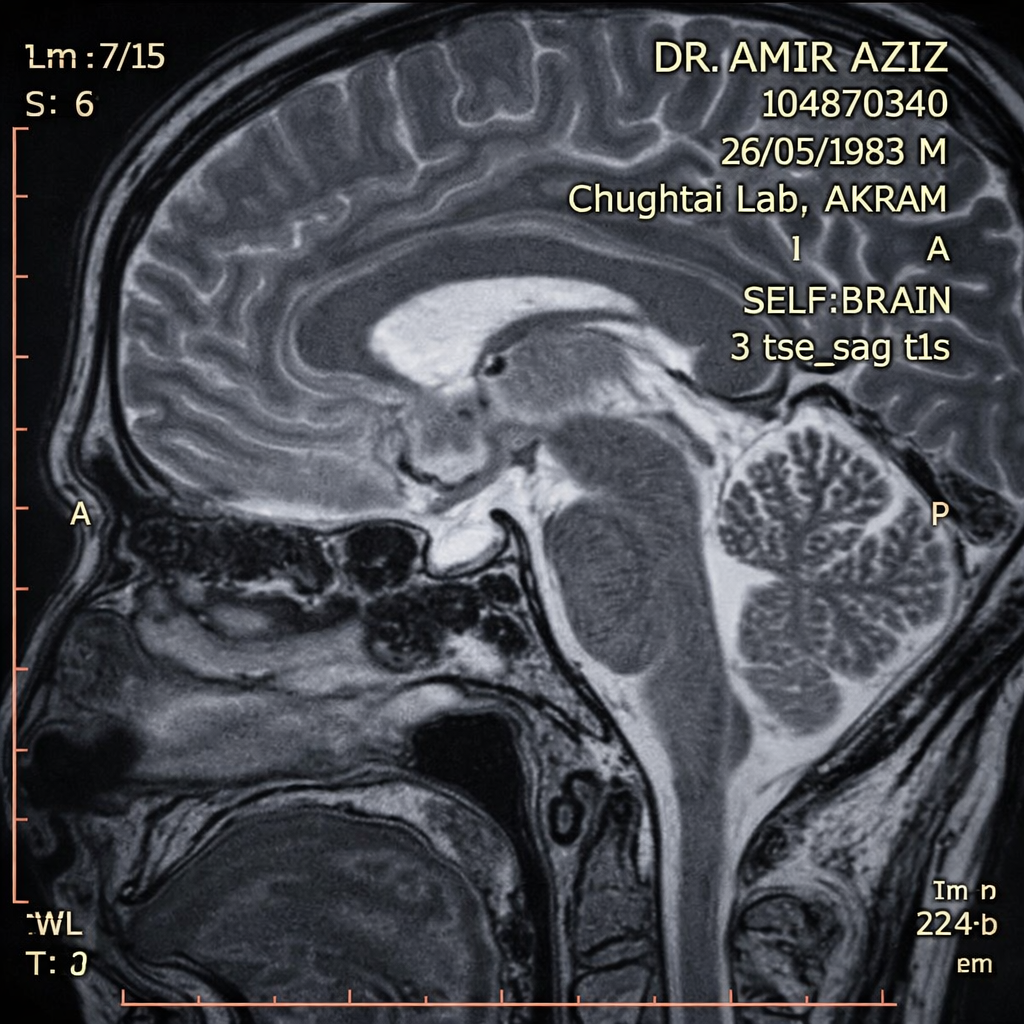

🧲

ImagingMRI Pituitary — Findings

Pituitary Adenoma Schematic

Schematic representation — not to scale

MRI FindingDescription

Lesion typeMicroadenoma (<10mm)

Dimensions7 × 6 mm

LocationPituitary gland

GH-secretingConfirmed

Cavernous sinusNot invaded

Optic chiasmNot compressed

Microadenoma (<10mm) carries higher remission rates with transsphenoidal surgery vs. macroadenoma. Absence of cavernous sinus invasion is a favourable prognostic indicator.